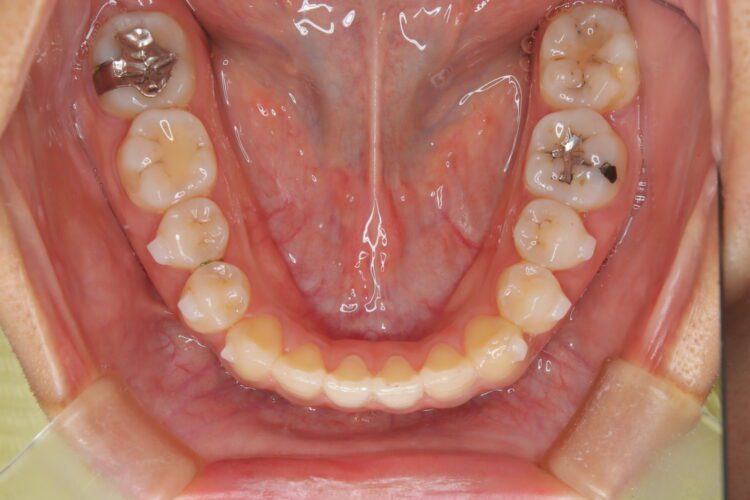

受け口の改善を主訴にご来院された患者様です。

軽度の下顎前突と診断し、マウスピース矯正装置(インビザライン)を用いて治療を行うこととしました。

治療の際はゴム掛けが必要になりましたが、患者様が非常に真面目に使用してくださったおかげで、スムーズに治療が進みました。途中の海外赴任という大きな予定変更がありましたが、そのご努力の甲斐あって、無事に渡航前に矯正を完了することができました。